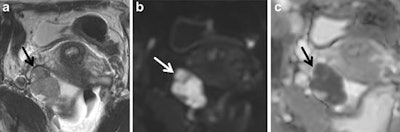

They now recommend DWI be applied for solid adnexal masses with low T2 signal because such masses with low DWI signal can be regarded as benign. However, any solid adnexal mass that shows intermediate or high DWI signal requires further assessment by contrast-enhanced T1-weighted imaging, ideally with dynamic contrast-enhanced MRI, they added.

Several studies have confirmed DWI has a valuable role in MR imaging of the adnexal mass, but the correct DWI technique is ensured by using a high enough b-value to suppress any high signal intensity from freely diffusing water molecules, while keeping sufficient signal-to-noise ratio to identify pathology that has restricted water diffusion, the authors noted.

"The added value of DWI is in assessing nonfatty, nonhemorrhagic pelvic masses that are entirely solid or complex masses that are either septate cysts or complex solid and cystic masses," the authors noted.